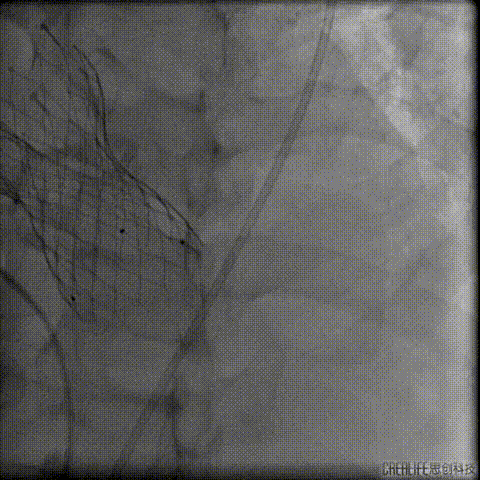

预扩主动脉瓣

左冠血流受到影响

予ECOM支持

患者恢复自主心率